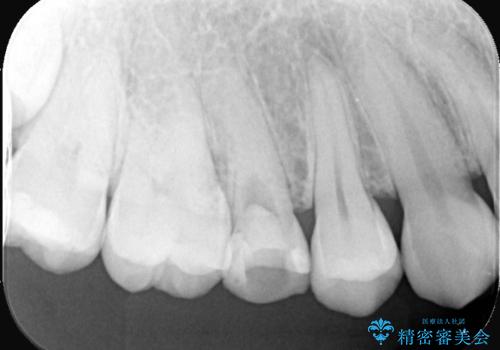

右上5番目の歯が根管治療途中となっており、前医院にて根管が狭く治療が難しいと言われてしまいセカンドオピニオンで当院にいらっしゃいました。

右上5番レントゲン写真上では根管が確認しずらく、根管の狭窄が予想されました。マイクロスコープを使用し、根尖部まで器具を到達させ十分根管洗浄を行うことができました。